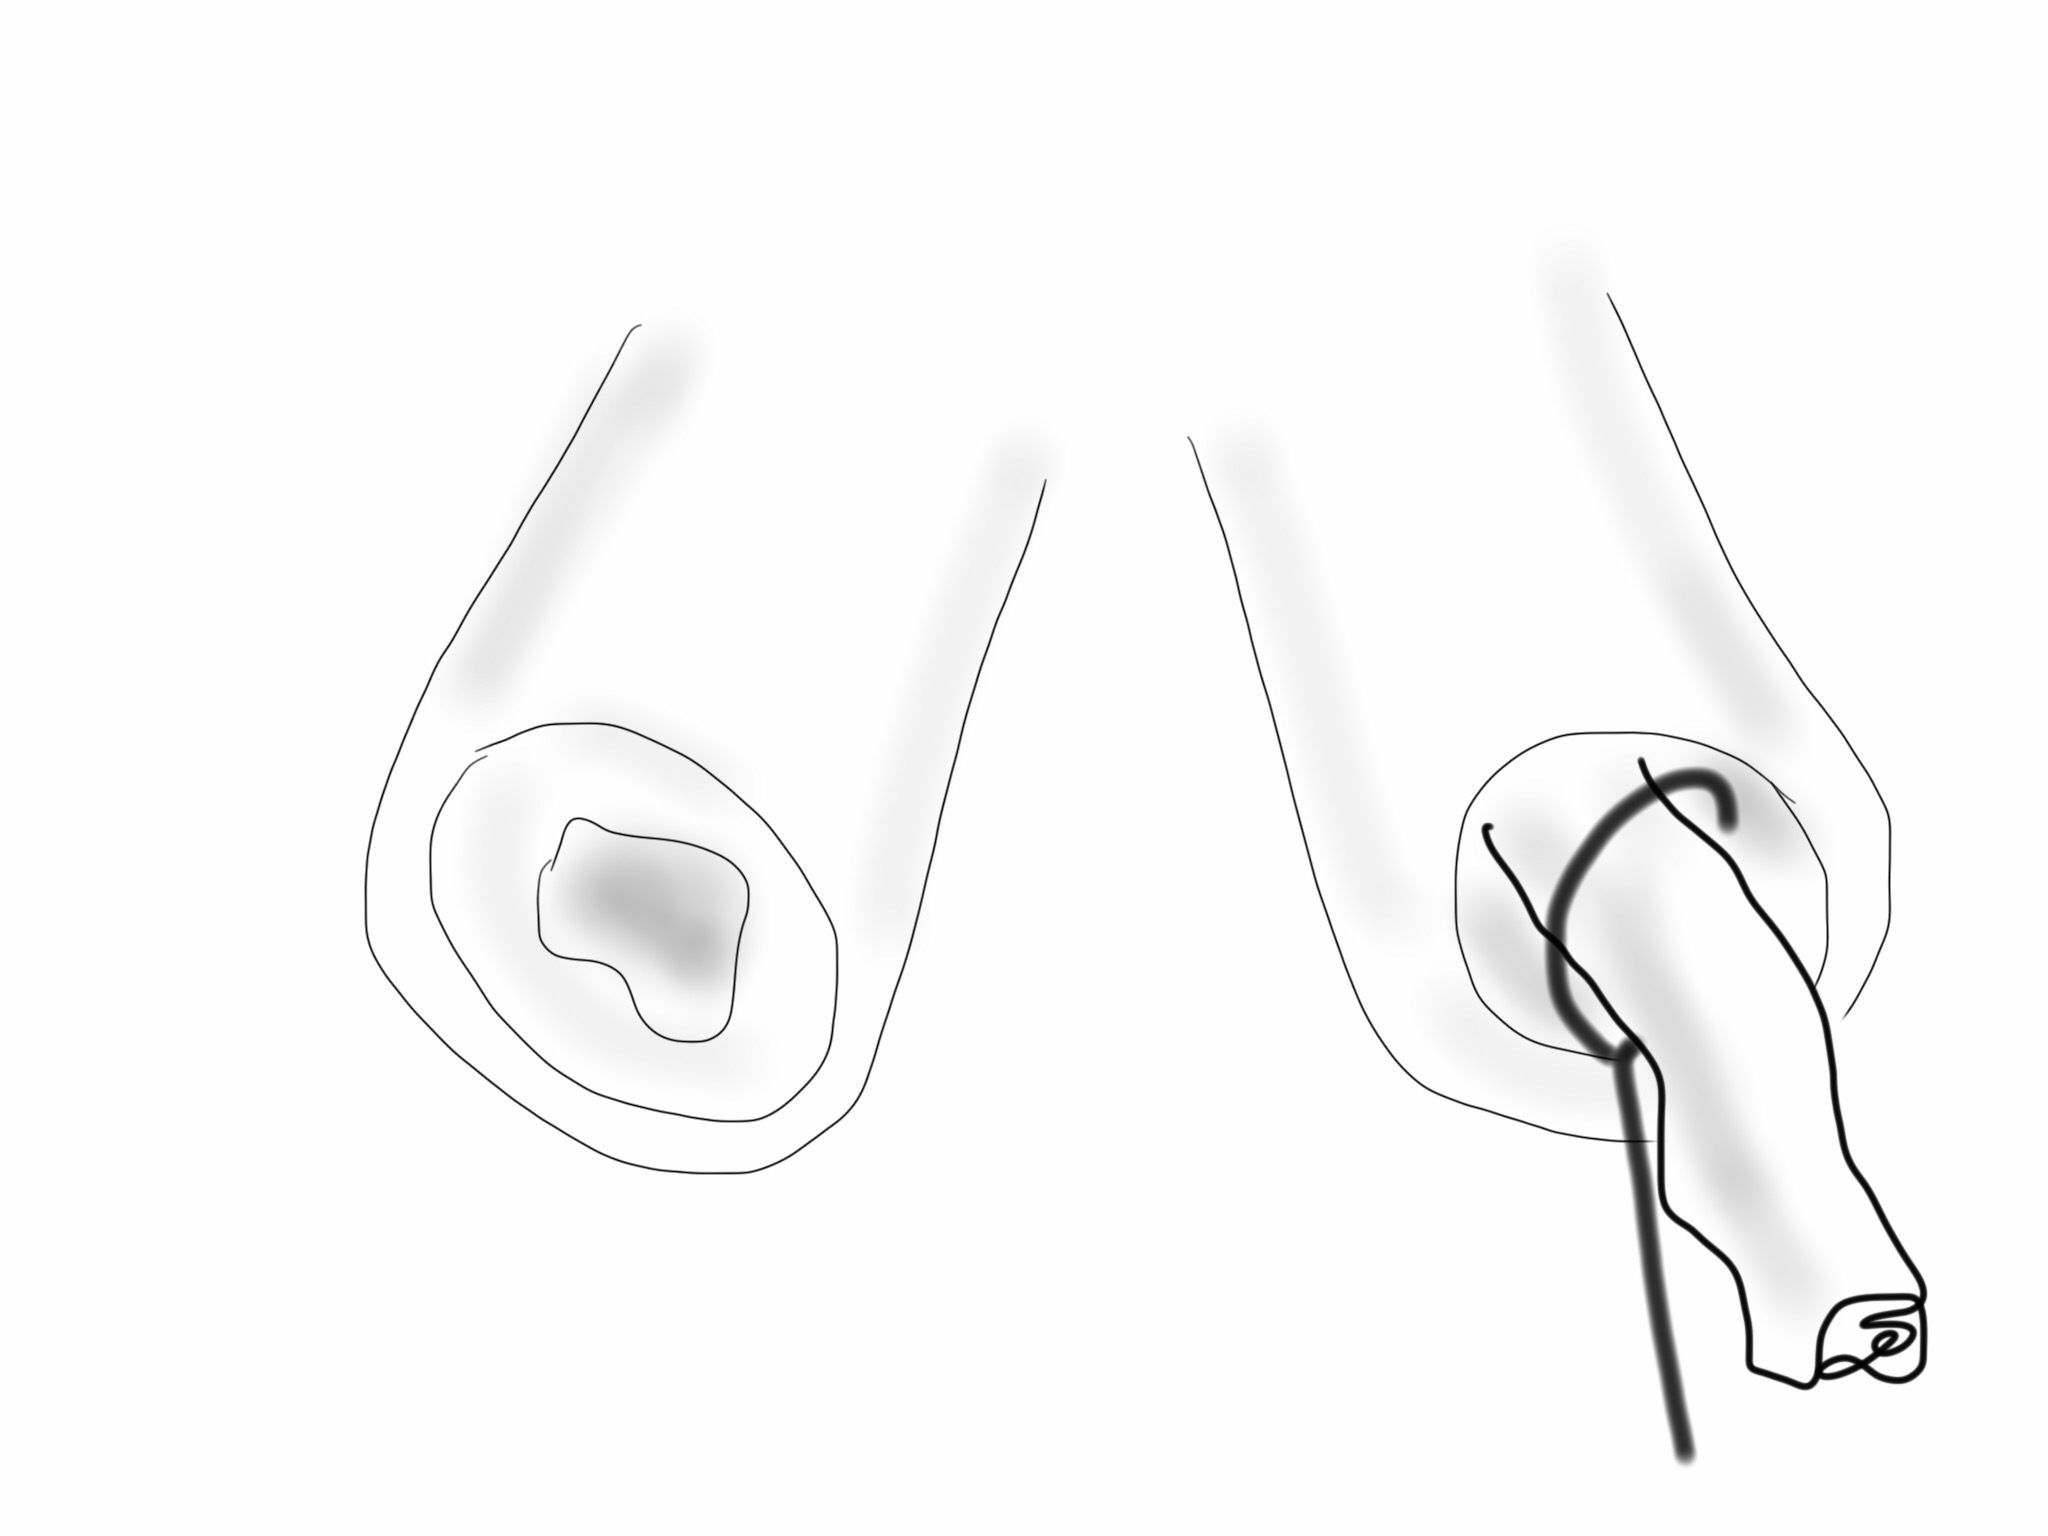

The common femoral endarterectomy is done from its distal most point and the Vollmer ring is used to mobilize the plaque. A Moll Ring Cutter (LeMaitre Vascular) is then used to cut the plaque.

The plaque is extracted and re-establishes patency of the EIA.

The plaque end point is typically treated with a stent -in this case, the common iliac plaque was also treated.